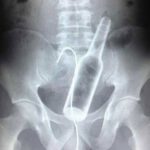

「【意味不明】腹痛を訴えて病院に来た中国人男性、ガラス瓶を飲み込んでいたことが発覚!」に戻る